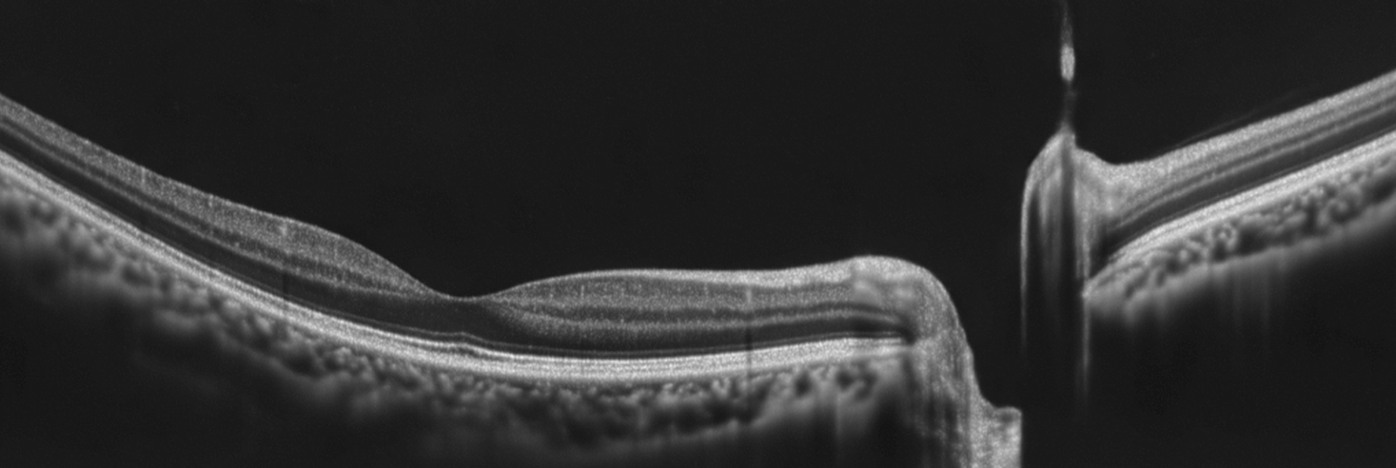

OCT is a new imaging technique that provides high resolution and cross-sectional images of the eye. An OCT scan allows microstructures of the eye to be imaged and shows different colour-coded layers of the retina. It is particularly useful in the diagnosis and management of eye conditions such as age-related macular degeneration, diabetes, macular hole and glaucoma.

OCT uses high definition scanning and 3D imaging to be able to penetrate the soft tissues of the eye, in effect to peel back the layers and see what’s happening within the tissue. The results can be used to identify many eye diseases at an incredible early stage and to monitor for change over time with great sensitivity. Never before has it been so easy to pinpoint the exact location of concern!